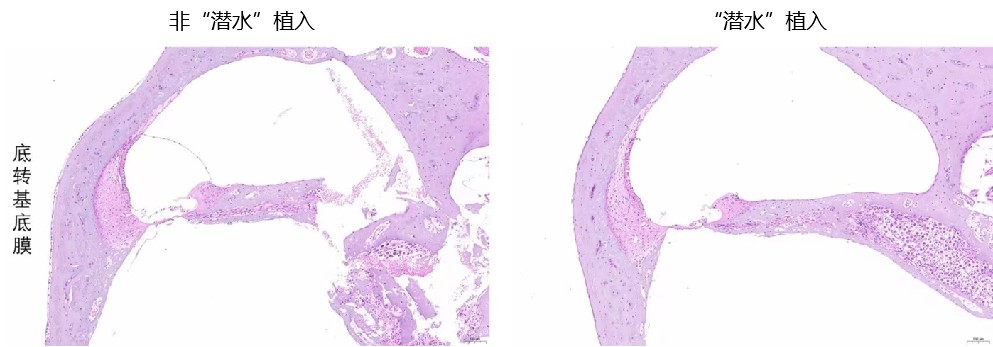

潜水插入技术明显减轻电极对耳蜗基底膜损伤

据介绍,团队在新技术通过科学、严密的动物实验,证实了“潜水”植入技术的安全性和有效性,团队通过反复的对比、改进,明确了“潜水”植入的最佳参数。